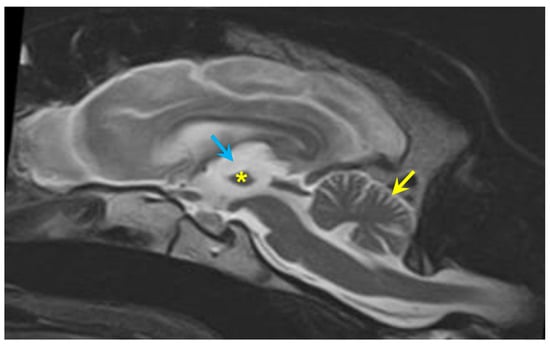

3.1. Disease Phenotype